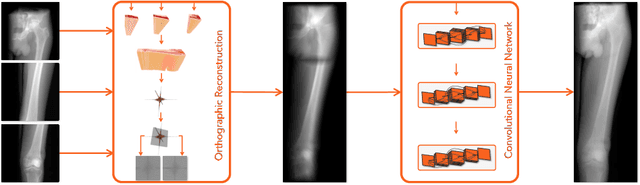

Stitching images acquired under perspective projective geometry is a relevant topic in computer vision with multiple applications ranging from smartphone panoramas to the construction of digital maps. Image stitching is an equally prominent challenge in medical imaging, where the limited field-of-view captured by single images prohibits holistic analysis of patient anatomy. The barrier that prevents straight-forward mosaicing of 2D images is depth mismatch due to parallax. In this work, we leverage the Fourier slice theorem to aggregate information from multiple transmission images in parallax-free domains using fundamental principles of X-ray image formation. The semantics of the stitched image are restored using a novel deep learning strategy that exploits similarity measures designed around frequency, as well as dense and sparse spatial image content. Our pipeline, not only stitches images, but also provides orthographic reconstruction that enables metric measurements of clinically relevant quantities directly on the 2D image plane.